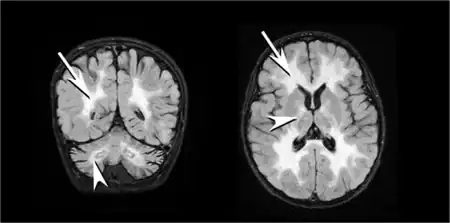

| T2 weighted axial scan of a human brain at the level of the caudate heads demonstrates marked loss of posterior white matter, with reduced volume and increased signal intensity. The anterior white matter is spared. Features are consistent with X-linked adrenoleukodystrophy. | |